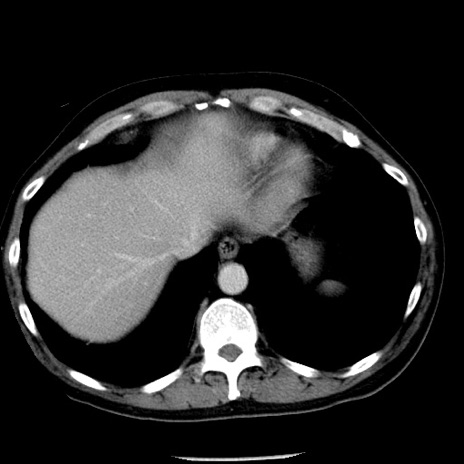

症例29(横断像)

【症例】40歳代男性

【現病歴】2日前から胃痛あり。徐々に周期的な激痛に変化した。本日になっても激痛があるため受診。

【身体所見】意識清明、BT 38-39℃台あり、腹部:膨満、やや硬、右下腹部に圧痛あり。

【データ】WBC 8500、CRP 23.26